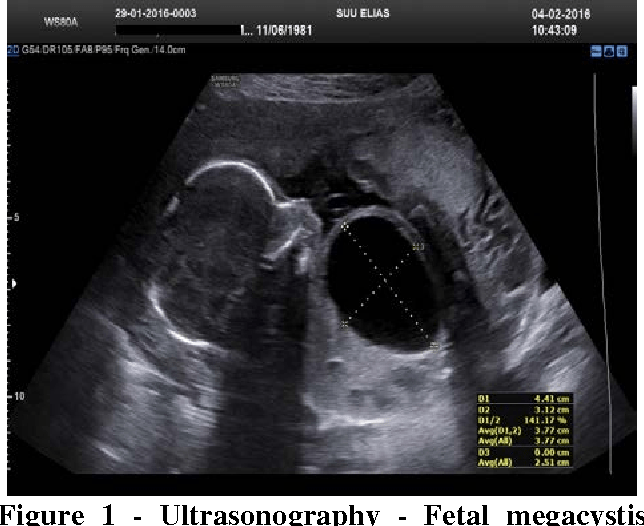

This type of CAKUT is characterized by a distended bladder on prenatal ultrasound

What is Posterior Urethral Valve?